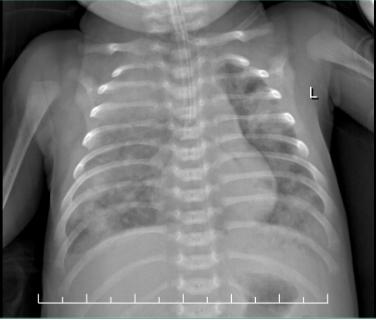

患儿入院后的肺部CT显示:两肺感染性病灶并多发肺脓肿形成。其肺部面临脓肿的侵蚀及炎症的破坏下能募集到的肺部有效通气极为有限,同时发热仍间断的出现,要在造成严重并发症之前,治疗在争分夺秒的同时进行。

患儿入院时的胸部X线片,两肺几乎成“白肺”